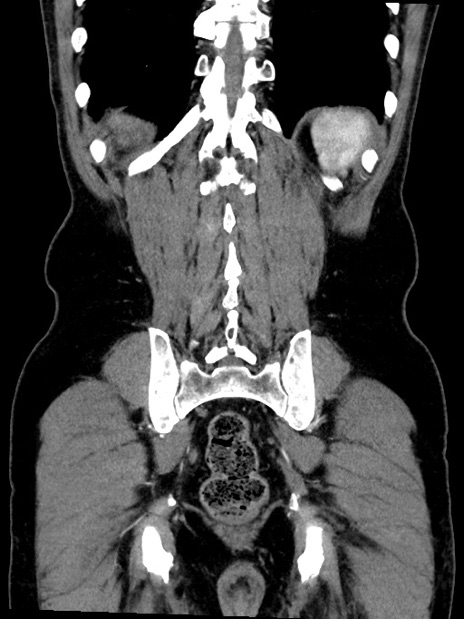

症例35(冠状断像)

【症例】70歳代 男性

【主訴】腹部膨満、嘔吐

【現病歴】昨日より腹部膨満感出現。本日増悪し、仙痛出現。嘔吐あり、受診。

【既往歴】糖尿病、胆摘後

【身体所見】BP 149/80mmHg、HR 74/min、BT 35.9℃、腹部:膨満、軟、圧痛なし。腸雑音減弱あり。上腹部正中切開瘢痕あり。

【データ】WBC 13500、CRP 1.72